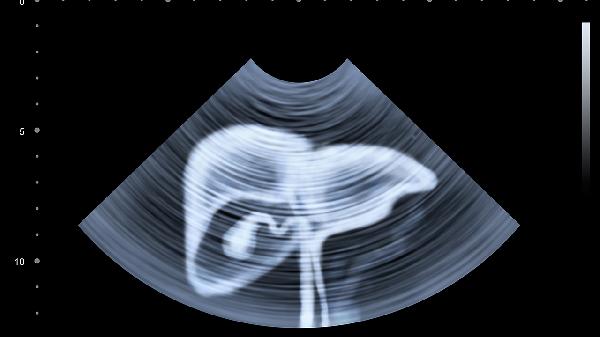

丙肝患者需建立規(guī)律作息,保證23點(diǎn)前入睡,避免熬夜加重肝臟負(fù)擔(dān)。建議每周進(jìn)行3-5次中等強(qiáng)度有氧運(yùn)動,如八段錦、快走等,每次30-45分鐘。嚴(yán)格戒酒并避免使用肝毒性藥物,每3-6個(gè)月復(fù)查肝功能、肝臟超聲及丙肝病毒定量。合并肝硬化者需定期進(jìn)行胃鏡檢查,預(yù)防食管胃底靜脈曲張破裂出血。保持樂觀心態(tài),可通過正念冥想緩解焦慮情緒,必要時(shí)尋求專業(yè)心理支持。